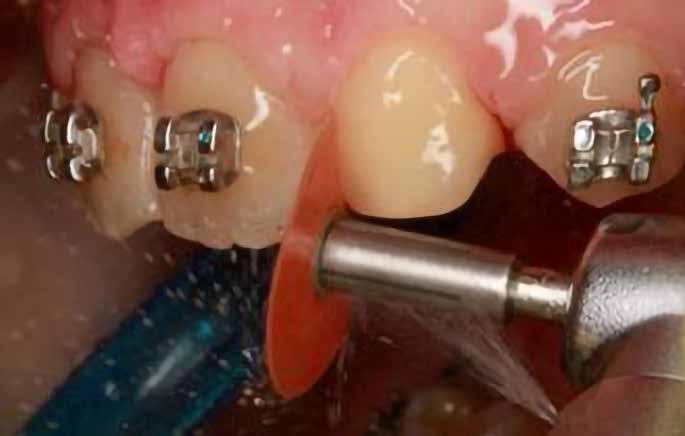

Kisőrlő becsiszolása

Ha a szemfog helyére mezializált kisőrlő intrúziójára nincs is szükség, a palatinális csücsök akkor is akadályozhatja a harapást és a szemfogvezetést [44]. Ezekben az esetekben elcsiszoljuk a palatinális csücsköt (8. a-b ábra) piros gyémántcsiszolóval (finom, 27-76 µm, éli formázóval – Rodentica speciális tűhegy 806314466514031, Komet 8833 vagy GD – lándzsa Rodentica 806314257514020, Komet 0640) gyorsítóban (max 160 000 fordulat/perc) vízhűtés mellett, min. 50 ml/perc [39]. Extra finom sárga gyémántcsiszolóval polírozunk, 10-36 µm szemcsézettséggel (sárga éli csiszoló Rodentica speciális tűhegyű 806314466504031, GD – sárga lándzsa alakú Rodentica 806314257504020) és narancs Sof-Lex korongokkal (3M finom, narancssárga-alumínium-oxid kristály 3-40 µm nagysággal, extra finom, narancssárga-sárga, 1-7 µm alumínium-oxid kristályokkal) könyökdarabban (25 000 fordulat/perc) legalább 50 ml/ min. hűtéssel. Az elcsiszolást több lépésben végezzük, és ezt helyi fluoridalkalmazás követheti.

8. a-b. ábra: A páciens a felső első kisőrlő palatinális csücskének elcsiszolása előtt (a) és (b) után, a szemfogvezetés kialakításához. A szemfog vesztibuláris felszínének befejezése.